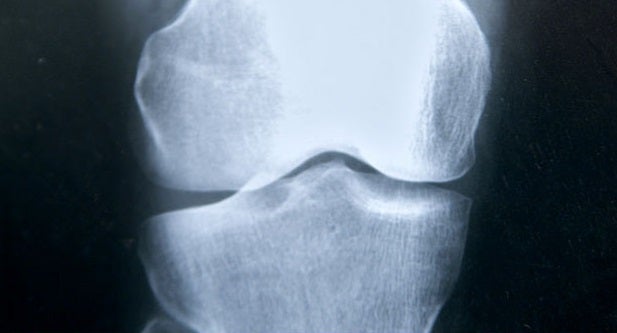

Osteoporosis: Solo el 30% de las mujeres la considera como un riesgo para su salud

En España, más de tres millones de personas padecen osteoporosis. En 2017 se registraron un total de 330.000 fracturas, cifra que aumentará en un 30 por ciento en 2030. A pesar de que continúa siendo la dolencia ósea más común, solo el 17 por ciento de las mujeres mayores de 55 años y el 30 por ciento de las mayores de 65 han preguntado alguna vez a su médico sobre su prevención y tratamiento.